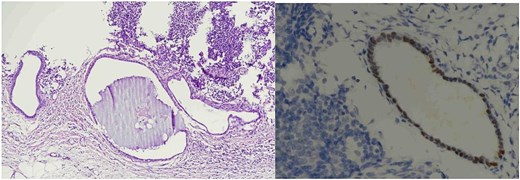

Histopathological analysis showed two reactive lymph nodes measuring 2.0 cm and 3.5 cm. Immunohistochemistry demonstrated positivity for pancytokeratin, estrogen receptor (ER), and CD10, consistent with endometrial tissue. Histopathological images of the lymph nodes are presented in Figs 1 and 2. No signs of malignancy were identified.

Lymph node endometriosis. Lymph node number 2, A: Hematoxylin/eosin stain × 100; B: Estrogen receptor immunostaining × 400.